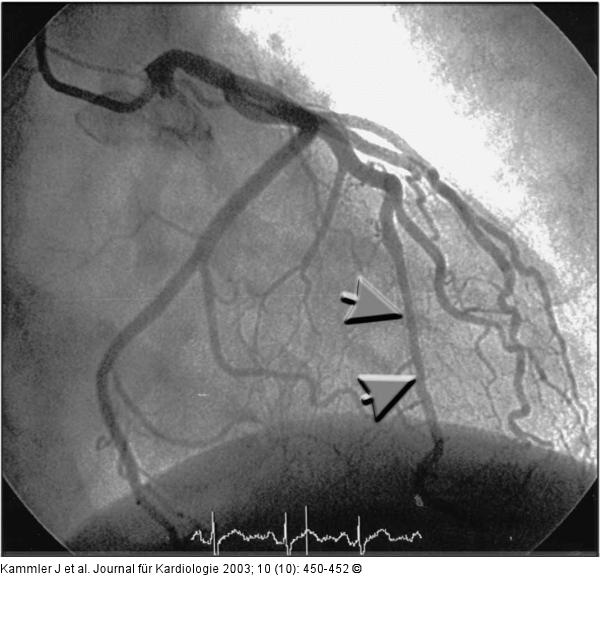

Abbildung 3: Arteria coronaria sinistra - Stent Angiogramm der linken Koronararterie 10 Monate nach Stentimplantation (systolische Phase): geringe diffuse Lumeneinengung im Bereich des implantierten Stents; keine systolische Komprimierung (siehe Pfeile). |

Angiogramm der linken Koronararterie 10 Monate nach Stentimplantation (systolische Phase): geringe diffuse Lumeneinengung im Bereich des implantierten Stents; keine systolische Komprimierung (siehe Pfeile). |